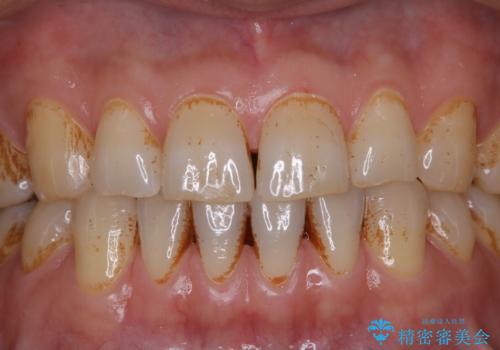

タバコとコーヒーによる頑固な着色落とし

- 毎日の喫煙とコーヒーを飲むことにより、ひどく着色がついてしまったとのことです。PMTC60分コースを行いました。

毎日丁寧に歯磨きをしていても、日常生活での飲食物などにより着色してしまうことはあります。

PMTC(保険外治療)は、毎日の歯磨きで落としきれない汚れや、コーヒ、紅茶・タバコのヤニなどの着色も除去します。目には見えない歯と歯の間・歯肉の境目などに残っているプラーク(歯垢)もしっかり取り除きます。PMTCでは専門的な機械や材料を使用して、徹底的に汚れを除去するため、虫歯・歯周病・口臭予防などにつながります。